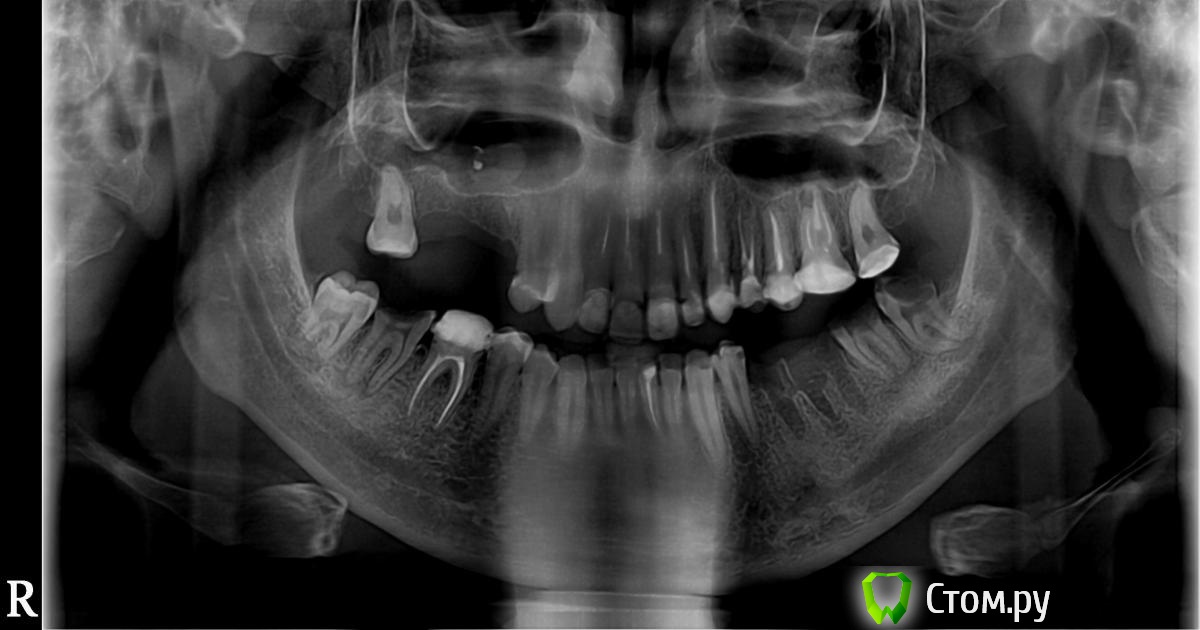

ohspb Опубликовано 7 апреля, 2014 Автор Поделиться Опубликовано 7 апреля, 2014 (изменено) снизу слева 5,6 отсутствуют, 7,8 под удаление. справа 7 - удаление. остальные все живые.сверху 6 слева под удаление, 5,6 справа отсутствуют. Снимка сейчас нету.Планирую имплантацию, но сначала хочется разобраться с передними зубами.Сверху все зубы кроме 3 и 4 справа мертвые Изменено 7 апреля, 2014 пользователем ohspb Ссылка на комментарий

ohspb Опубликовано 10 апреля, 2014 Автор Поделиться Опубликовано 10 апреля, 2014 Решил начать с жевательных тогда. Вот снимок прикрепляю Ссылка на комментарий

M@estro Опубликовано 12 апреля, 2014 Поделиться Опубликовано 12 апреля, 2014 (изменено) Вам грамотный стоматолог нужен. У многих Ваших зубов - последний шанс,но он есть. Неграмотный стоматолог либо предложит не трогать - и "обточить" как есть,либо удалит ещё несколько зубов без попыток сохранения - и предложит конструкцию на иплантатах. Ситуация непростая,но решаемая. Изменено 12 апреля, 2014 пользователем M@estro 2 Ссылка на комментарий